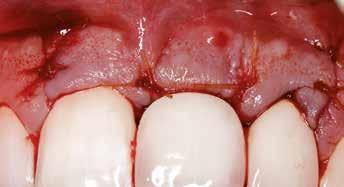

Az implantátum körüli lágyszövet defektusok (papilla hiánya, csökkent lágyszövettérfogat, ínyrecesszió, dehiszcencia, színeltérés) kialakulása viszonylag gyakori komplikációnak számít és befolyásolja az implantátum hosszú távú stabilitását, valamint az esztétikai eredményt (1, 2). Számos tényező befolyásolhatja az ilyen defektusok kialakulását. Csontvesztés a faciális falon, illetve a vékony biotípus elősegítheti egy esetleges implantátum körüli recesszió kialakulását (3). A két milliméternél vékonyabb lágyszövet pedig fokozottabb marginális csontvesztést okozhat (4, 5), amelynek következményeképpen az implantátum szabaddá válhat. Ha az ínyrecesszió mellett nem elegendő a keratinizált íny mennyisége, úgy nehezebb azt megfelelően tisztítani, ami gyulladáshoz és esztétikai problémákhoz vezethet (6). Lágyszövet augmentációt alkalmazhatunk az implantátum felszabadításakor, azonnali implantációval együtt, papillák rekonstrukciójához, keratinizált ínyszélesítéshez, biotípus vastagításhoz és a gerinckontúr helyreállításához egyaránt (7).

Egyre nagyobb az igény az implantátum körüli lágyszövet defektusok kezelésére, mivel azonnali implantáció után gyakran alakulhat ki ínyrecesszió, a szövetek átépülése miatt. Vékony lágyszövet (< 2 mm) esetén szürkésen áttűnhet az implantátum vagy a felépítmény, illetve a lágyszövet hegesen gyógyulhat, ami egyaránt lágyszövet-korrekciót tehet szükségessé (8, 9, 10).

Számos sebészi technikát, valamint sebészi és protetikai módszerek kombinációját leírtak már az ilyen defektusok kezelésére. Sok érvet találhatunk, amely az implantátum felszabadításakor (second-stage surgery) a periimplantáris nyálkahártyán végzett beavatkozások mellett szól. Az irodalmi áttekintés leszögezi, hogy esztétikai régióban, illetve a megfelelő plakk-kontroll érdekében szükséges a keratinizált íny regenerációja, hogy az implantátum körüli szövetek stabilitása biztosított legyen (11). A lebeny kialakítása a következőktől függ: az ínyrecesszió kiterjedése, a vesztibulum mélysége, a nem elmozduló nyálkahártya szélessége és az interproximális szövetek térfogata (1). A klasszikus sebészi módszereknél általában apikálisan vagy laterálisan eltolt lebenyeket használunk az implantátum felszabadításakor. Ezeket a technikákat kombinálhatjuk szabad ínylebeny (free gingival graft) átültetéssel, amikor a keratinizált mukóza szélessége minimális. Az apikálisan eltolt lebeny vagy vesztibulumplasztika kombinálása szabad ínylebennyel vagy szubepiteliális kötőszöveti grafttal az egyik legjobban kutatott technika. Az eredmények alapján 1,15 ± 0,81 mm és 2,57 ± 0,50 mm közötti keratinizált ínyszélesség nyerhető, valamint megfelelően fedhető a szabaddá vált implantátumfelszín (12). A keratinizált íny szélesítéséhez apikálisan eltolt lebeny kollagén mátrixszal kombinálva kisebb morbiditást jelent és a műtét ideje is rövidebb, illetve szinte ugyanolyan hatékony, mint a szabad ínylebennyel végzett műtétek (13). Szuprakresztális és/vagy dehiszcencia típusú defektusok esetén is alkalmazhatóak a szabad autológ epiteliális graftok (14). Az autológ graftot alkalmazó módszerek sokkal hatékonyabbak az implantátum körüli lágyszövet-vastagításban és az esztétika javításában, mint a graft nélküli eljárások (15, 16). Egy szisztematikus irodalmi áttekintés megállapította, hogy az ínyvastagításra alkalmazott autológ graftok jelentősen csökkentik a marginális csontvesztést hosszú távon, valamint apikálisan eltolt lebennyel kombinálva megnövelik a keratinizált íny szélességét, ami jobb szondázási vérzésindexet eredményez és a marginális csontszintváltozás sem lesz annyira drasztikus (17). Az imént leírt technikákkal kiváló eredmény érhető el az implantátumok körül, azonban figyelembe kell vennünk a velük járó morbiditást (seb a donorterületen, ami leggyakrabban a szájpadlást jelenti), a dinamikus lágyszöveti változásokat (recidíva) és a hosszabb gyógyulási időt. Ezekkel a technikákkal kompenzálható a volumenveszteség és kezelhetők a kisebb recessziók, azonban kevésbé egyértelmű mélyebb vagy nagyobb recessziók és a papillavesztések kezelése (1). Ezeket a nehézségeket elkerülhetjük nyeles epitelizált vagy nyeles kötőszöveti lebenyekkel kollagén mátrix alkalmazásával vagy anélkül (18). A

A kutatások az implantátumok körüli lágyszövetek egészségére fókuszálnak, mivel kulcsfontosságú a megfelelő feszes ínyszélesség és a megfelelő ínyvastagság a biológiai komplikációk és a marginális csontvesztés megelőzésében (4, 5). Nem elmozduló, feszes szövetek szükségesek az implantátum körül, hogy ne alakulhasson ki periimplantitis és megtartható legyen a csontszövet (24, 25). Az implantátumok körüli lágyszövetek kondicionálására szolgáló technikák javasoltak azokban az esetekben, ahol bizonyos tényezők (konvex pótlás-implantátum kontúr, vékony íny, 3 mm-nél nagyobb implantátum platform-csontszint távolság, interproximális szövetvesztés, nem optimálisan pozicionált implantátum) befolyásolhatják a szövetek stabilitását (1). Az implantátum körüli lágyszövet hiányok kezelésével kapcsolatban nem sok irodalmi bizonyíték áll rendelkezésre (1.). Keratinizált ínyszélesítés területén egy szisztematikus áttekintés az apikálisan eltolt félvastag lebennyel és szabad ínylebeny átültetéssel végzett technikát hasonlította össze a szubepiteliális kötőszöveti grafttal vagy xenogén lágyszövetpótló anyaggal (12). Ugyanez az áttekintés átlag 28,0% és 96,3%-os recessziófedést írt, amikor koronálisan eltolt

A klasszikus apikális vagy laterálisan eltolt lebeny technika (epitelizált grafttal kombinálva) megbízhatósága ellenére számos komplikációt jelentettek (graft elhalás, zsugorodás, recesszió recidívája) (17). Ezenfelül a kötőszöveti graftot vagy kollagén mátrixot alkalmazó technikák is eredményezhetnek mobilis implantátum körüli szöveteket, ezáltal veszélyeztetve a implantátum és a körülötte lévő szövetek stabilitását, ami biológiai komplikációkhoz vezethet (26).